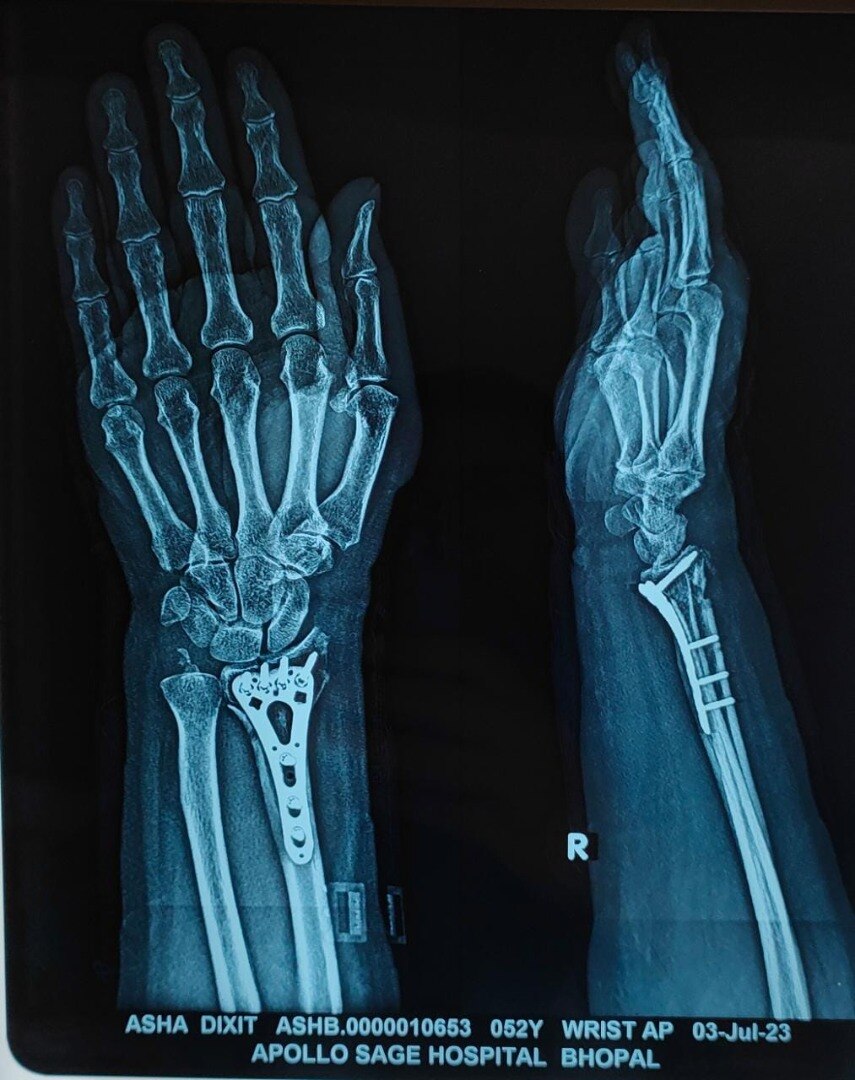

Welcome to the world of orthopedic excellence, where your health and well-being are our utmost priorities. Dr. Chetan Singh , an accomplished orthopedic surgeon, has been a dedicated practitioner in the vibrant city of Bhopal for the past 8 years. His unwavering commitment to providing exceptional orthopedic care has earned him a reputation as a trusted healthcare professional in the region. Meet Dr. Chetan Singh is a highly skilled orthopedic surgeon who has dedicated his career to improving the lives of patients suffering from orthopedic conditions. His educational journey began with the completion of an MBBS degree from Devi Ahilya Vishwa Vidyalaya, Indore, M.P. in 2015, where he laid the strong foundation for his medical expertise. Driven by his passion for orthopedics and a desire to offer the best care possible, Dr.Chetan Singh continued his educational journey. In 2019, he successfully achieved a Master of Surgery (MS) in Orthopedics from Madhya Pradesh Medical Science University, Jabalpur. This rigorous training equipped him with the knowledge, skills, and advanced techniques necessary to diagnose, treat, and manage a wide spectrum of orthopedic conditions.